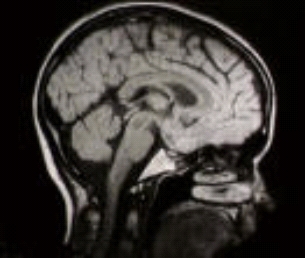

Tomography refers to imaging by sections. It is used in various different scenarios, such as producing medical images of the inside of the body (without cutting it open), for seismic and atmospheric imaging, and in material sciences to analyse structures of materials. And this variety of applications is reflected in the different types of tomography that are used.

In magnetic resonance tomography for instance (MRT, or more familiarly called MRI – magnetic resonance imaging), the sectioning/slicing is done by using strong magnetic fields and radio waves to slice the body. The data measured from MRT are, roughly, samples of the Fourier transform of an image of the water density inside the body. The reconstruction task is then to reconstruct an image, showing the water density in the body, from its Fourier samples. (You can read more here about Fourier transforms of images.)

A CT scan of the inside of a head.

In computer tomography (CT) on the other hand, high energy x-rays are slicing through the body. The x-rays are sent into the body with a particular energy. As the x-ray travels through the body energy is accumulated or lost, depending on the type of tissue the x-ray travels through. And at the other end, the energy of the x-ray emerging from the body is recorded.

The data measured from CT is formalised mathematically as line integrals through the various tissues in the body: integrals over the image density along lines of different angles and different positions through the body (you can think of an integral as roughly as the accumulation of something over some interval). The mathematical problem is to reconstruct the image from these line integrals.